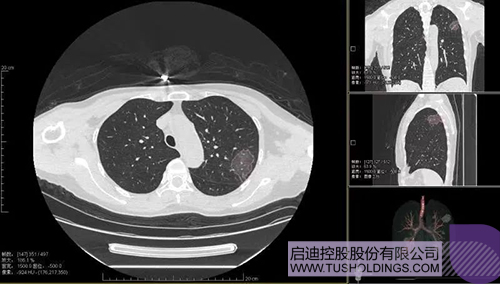

2020年2月11日,啟迪科服投資企業—神州德信推出新冠肺炎檢測及量化智能分析系統,積極助力一線醫務人員科學精準防疫。

2020年3月4日,繼由啟迪之星和啟迪裕麟參與投資的產學研一體化項目被《新聞聯播》報道后,由啟迪科服投資企業與西安交大聯合研發的新冠肺炎AI數字診斷技術亦被《新聞聯播》報道。